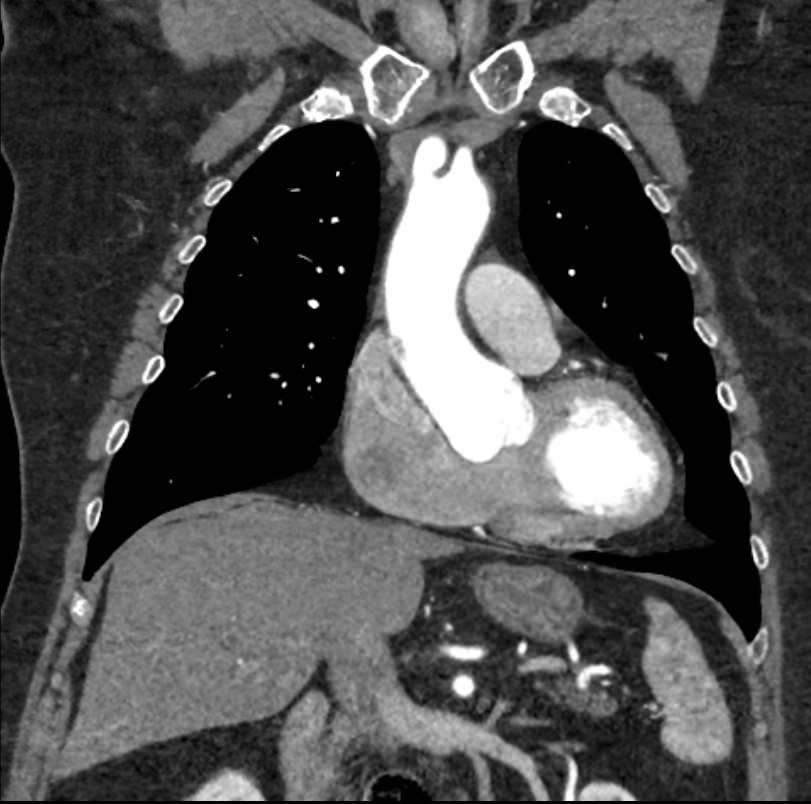

Грудная аорта делится на несколько отделов – восходящий отдел аорты, дуга аорты и нисходящий отдел. Корень аорты отходит непосредственно от левого желудочка, в его состав входят синусы Вальсальвы от которых берут начало коронарные артерии. После корня, прослеживается тубулярная часть восходящего отдела аорты, которая переходит в дугу аорты.

Дуга аорты дает начало брахиоцефальным артериям, которые питают головной мозг и верхние конечности. Затем следует нисходящий отдел аорты, распространяющийся через отверстие в диафрагме. От грудного отдела аорты отходят висцеральные артерии, кровоснабжающие органы средостения: бронхиальные, пищеводные, перикардиальные, медиастинальные артерии.

Одним из информативных методов диагностики сосудистой патологии является мультиспиральная компьютерная томография грудной аорты и ее ветвей (КТ-ангиография). Метод сканирования при помощи рентгеновских лучей и цифровой обработки данных позволяет получать послойные снимки сосудов и трехмерные реконструкции сосудистой системы в мельчайших подробностях.

Для того, чтобы качественно визуализировать сосудистую систему КТ-ангиография предусматривает в обязательном порядке применение контрастного усиления. Йодсодержащее контрастное вещество вводится пациенту внутривенно и, благодаря способности контраста поглощать рентгеновские лучи, ярко контрастирует сосудистую систему на фоне окружающих тканей.

КТ-ангиография позволяет диагностировать аневризмы аорты, сосудистые аномалии развития, воспалительные изменения стенок сосудов, пристеночные тромбы, сужения просвета сосудов за счет сдавления извне близлежащими опухолевыми образованиями.